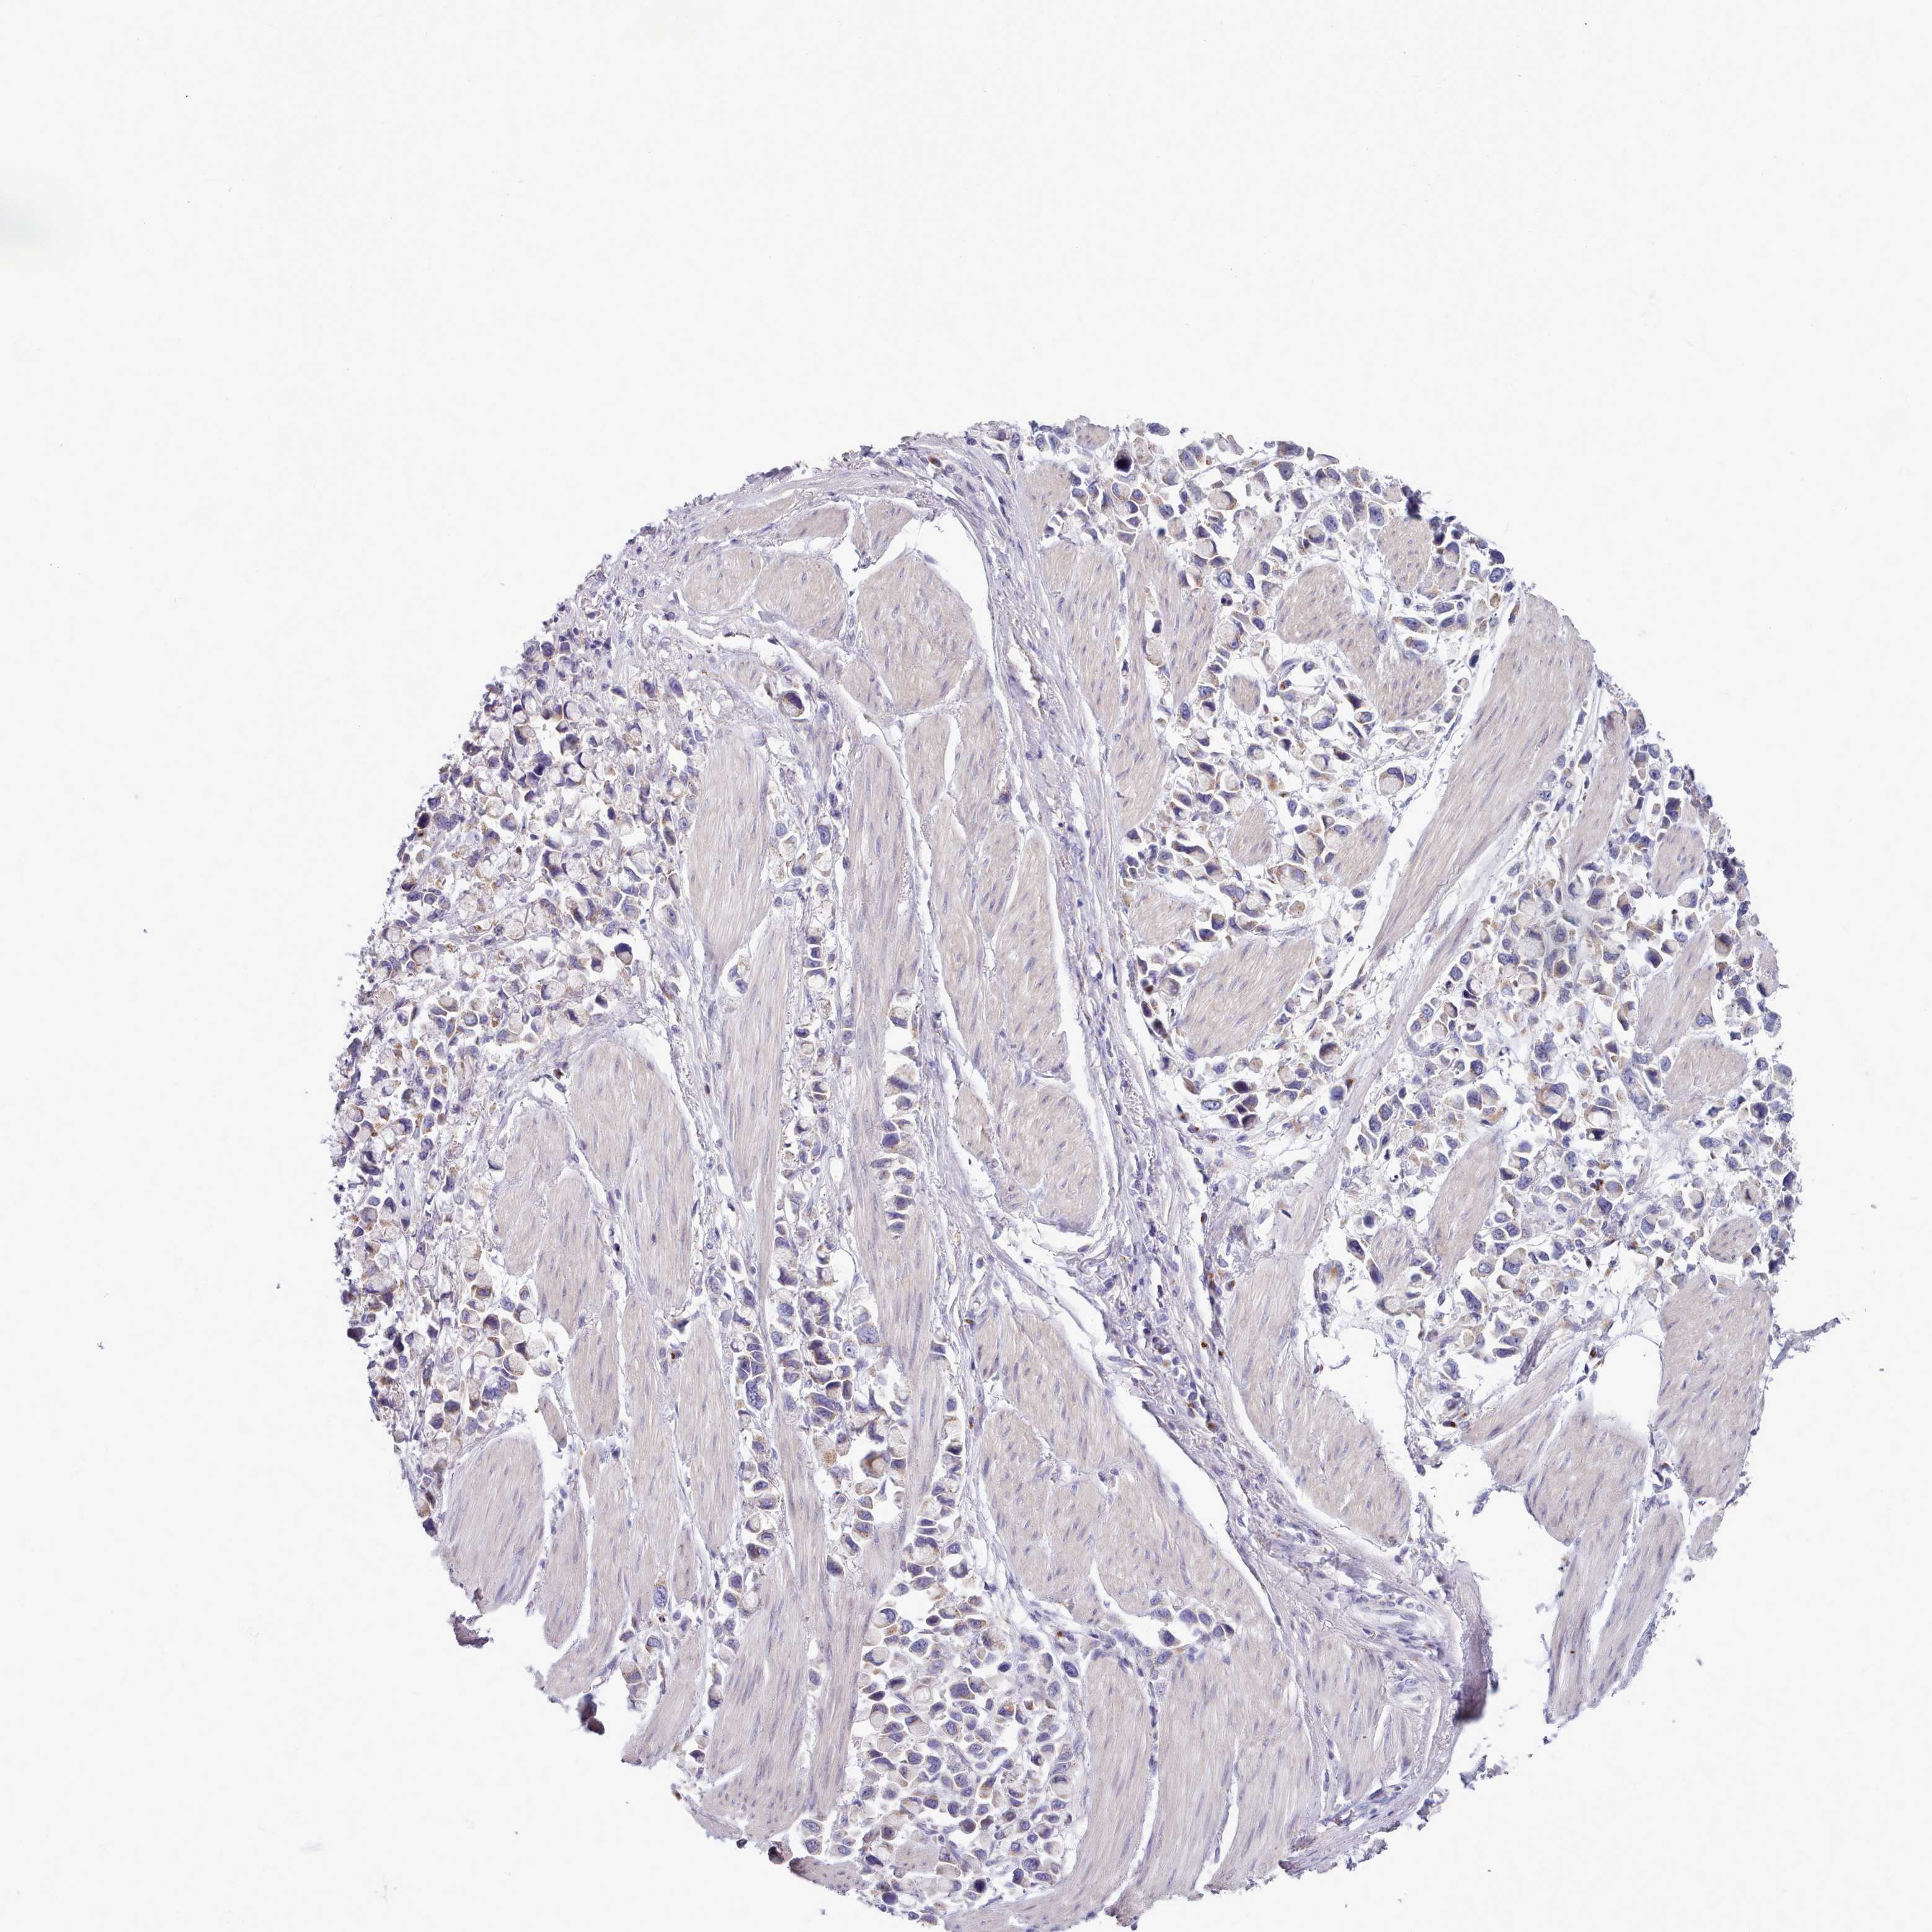

STOMACH CANCER - Protein expressioni

A mouse-over function shows sample information and annotation data. Click on an image to view it in a full screen mode. Samples can be filtered based on level of antibody staining by selecting one or several of the following categories: high, medium, low and not detected. The assay and annotation is described here.

Note that samples used for immunohistochemistry by the Human Protein Atlas do not correspond to samples in the TCGA dataset.

Antibody stainingi

Antibody staining in the annotated cell types in the current human tissue is reported as not detected, low, medium, or high, based on conventional immunohistochemistry profiling in selected tissues. This score is based on the combination of the staining intensity and fraction of stained cells.

Each image is clickable and will lead to virtual microscopy that enables deeper exploration of all samples and also displays staining intensity scores, fraction scores and subcellular localization as well as patient and tissue information for each sample.

Antibody HPA049340

Staining

High

Medium

Low

Not detected

Intensity

Strong

Moderate

Weak

Negative

Quantity

>75%

75%-25%

<25%

None

Location

Nuclear

Cytoplasmic/membranous

Cytoplasmic/membranous,nuclear

Adenocarcinoma, NOS